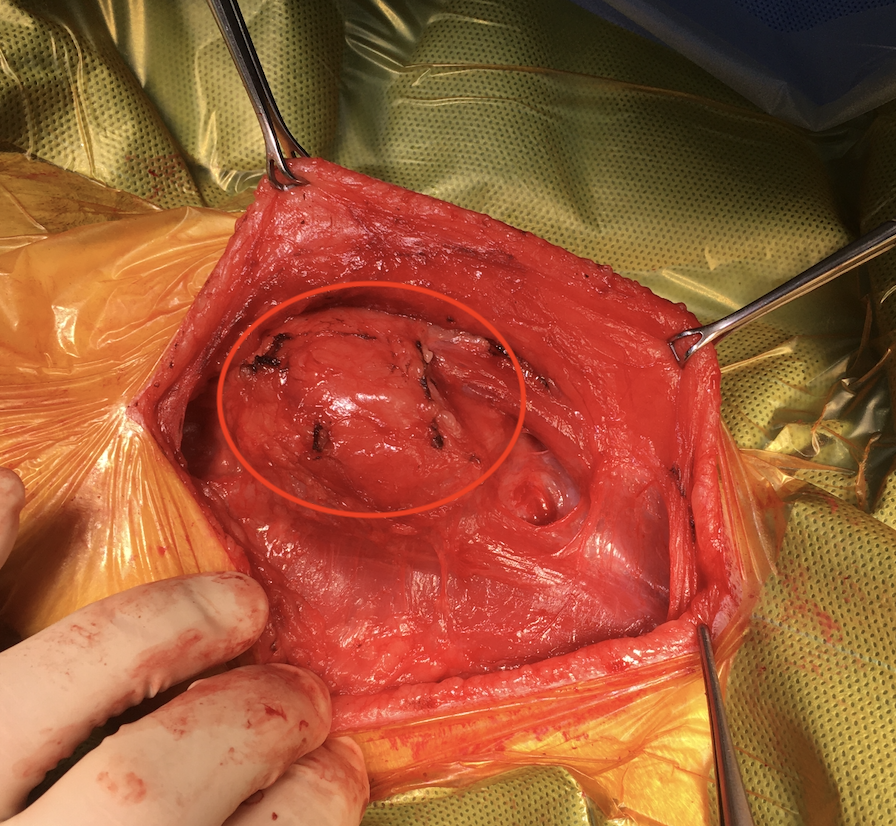

以下、手術時の写真となります(写真の左側が動物の頭側になります)。

苦手な方はご注意ください。

毛刈り後、腫れたリンパ節が盛り上がっているのが分かります(赤丸)。

皮膚と皮下の脂肪をを切開すると、リンパ節が確認できます(赤丸)。周囲の筋肉などとくっついているので、損傷しないように丁寧に分離していきます。